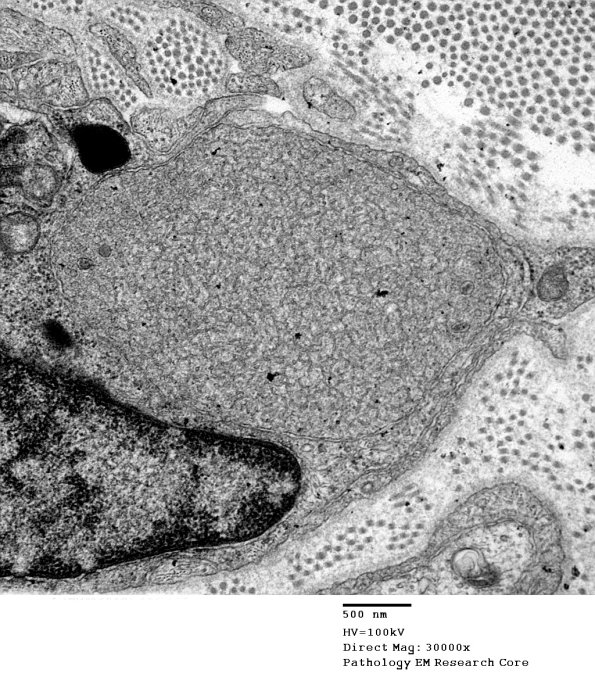

1B4A,B I find dystrophic axons particularly appealing. (electron micrographs)

Washington University Experience | PERIPHERAL NEUROPATHY | 22 VITAMIN E DEFICIENCY | 1B4A VitE Def (Case 1)_039 - Copy